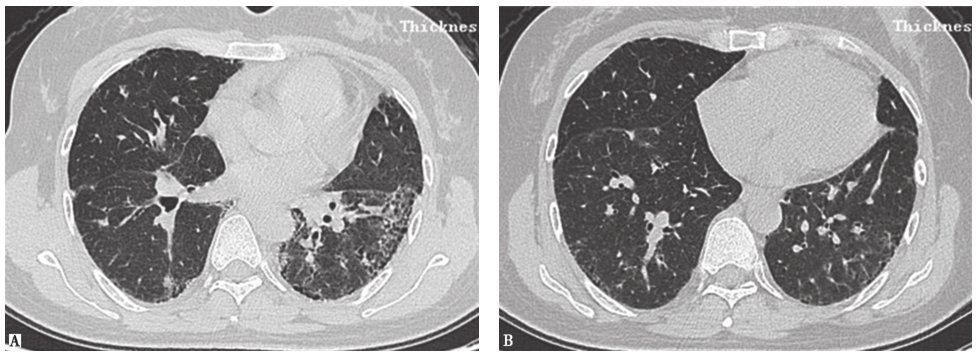

铁尘肺:是由于肺内巨噬细胞积聚三氧化二铁颗粒形成的,通常是吸入过多焊工烟雾造成的,故也称为焊工尘肺。绝大部分铁尘肺不引起肺纤维化和肺功能损害,可以无任何临床症状而在体检时发现。胸部CT可以发现双肺多发性边界不清的小叶中心型小结节影,少部分患者可发现线状影、斑片状实变影和广泛磨玻璃影(图11)。铁尘肺的诊断主要依据职业接触史和影像学特征,少数患者需要肺活检病理证实。本例患者自诉其接触金属粉尘可能主要为铁粉尘,但CT所示小结节影不如典型铁尘肺分布广泛,且临床症状相较于铁尘肺偏重,最终仍需病理结果来明确鉴别。

图11尘肺胸部CT表现

男性患者,42岁,经支气管肺活检病理证实为铁尘肺。胸部CT示两肺弥漫性磨玻璃样小结节影